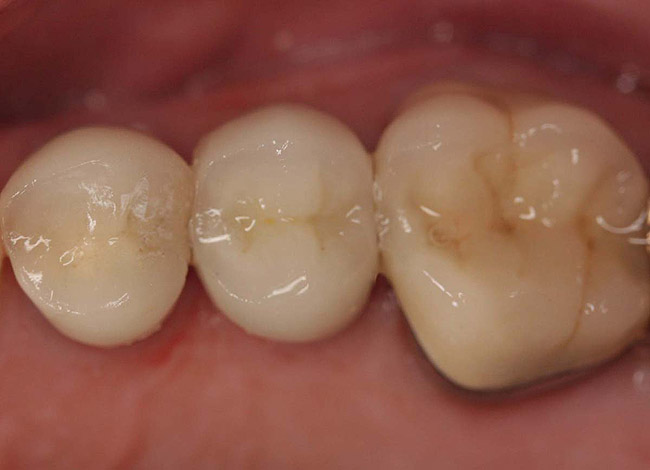

Case 2

A Class IIIN maxillary left second molar required restoration (Figure 6). Four canals, a chamber space, and little cross section of tooth structure were in the gingival third. Gutta-percha was removed with a Peeso reamer supplied in the C-1 kit. The canal was shaped with a bur in the kit, which was the same size as the corresponding post (Figure 7). The tooth structure was bonded with Brush & Bond™ (Parkell, www.parkell.com), and then the resin cement was spun into the canal with a lenticulo spiral. A C-1 white post was placed in the palatal canals (Figure 8). The C-1 White Post is a fiber-reinforced composite post, which flexes at the same rate as dentin to minimize root stresses.

Core build-up was completed with Absolute Dentin™ (Parkell, www.parkell.com) dual-cure high-strength core composite. There are variations on color and how materials cure. For example, Light-Core™ (Bisco, www.bisco.com) is a light-cured blue material, Encore® (Centrix, www.centrixdental.com) is a self-cure white material, and Para Core (Coltène Whaledent, www.coltene.com) is a dual-cure white or dentin-colored material. Material was placed directly and light-cured for 40 seconds (Figure 9). Final preparation for a PFM was completed (Figure 10). The final crown was placed (Figure 11).

Figure 10  Final tooth preparation to accept a PFM crown.

Figure 10

Figure 11  Final porcelain-fused-to-metal crown.

Figure 11